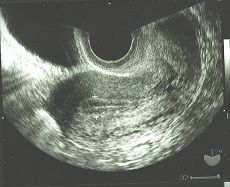

内膜は薄くなることが重要